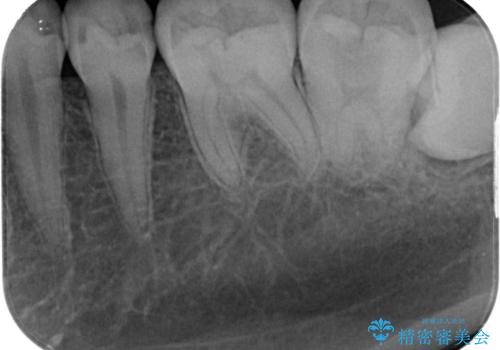

左下に虫歯が見つかった セラミックインレー修復

- 虫歯ができた気がするとのことで来院された患者様です。検査後セラミックインレーにて修復治療を行っていくことになりました。

拡大鏡視野下で虫歯の除去を行い、セラミックインレーに適した形に整えました。

歯と歯の間の虫歯をコンポジットレジンや保険のメタルインレーで治すと段差ができたりして清掃性が悪くなるので、セラミックインレー修復やゴールドインレー修復などの適合の良い詰め物で治療することをオススメします。